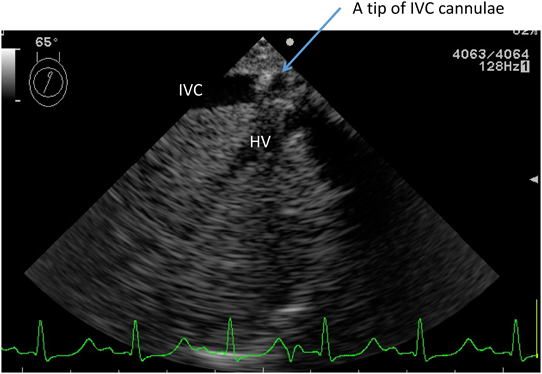

脱血カニューラ(Fig. 3)としては,先端がストレートのものと,直角になっているものとがある.挿入する位置は,右房,上下大静脈,無脾多脾症候群の際の肝静脈に挿入する.右房から上下大静脈に挿入する際は,ストレートタイプのものを用い,先端が直角になっているものは,上下大静脈や肝静脈に直接挿入する際に用いられることが多い.カニューラの挿入位置は重要で,深すぎる場合や,誤ったところに入ると,脱血が悪くなる.例えば,下大静脈脱血カニューラが誤って肝静脈に挿入されている状況で,長時間CPBを行うと,術後に著明な腹部膨満,腹水貯留等の合併症が起こるのでカニューラ先端位置確認の留意が必要である.最近では,術中食道エコーからの情報で,よい位置が確認できる(Fig. 4).脱血方法には,落差,ポンプ,吸引の三つの方法がある.落差脱血は,患児体を高い位置にすることにより,重力差で脱血する方法であり,自然な脱血方法である.ローラーポンプを用いて脱血する方法があるが,強制脱血することにより,回路内腔がつぶれて,脱血不良となったり,強い陰圧で,血管に損傷を与えたりする可能性がある.通常は途中に静脈ソフトリザーバーを設けて,過度の陰圧がかからないような工夫が必要である.吸引脱血は,貯血槽に陰圧をかけ,強制的に脱血する方法であり,現在はこの方法を用いている施設が多い.カニューラサイズを一サイズ小さくすることが可能な場合がある.

Fig. 4 Transesophageal echo shows a correct position of the tip of a venous cannula

IVC: inferior vena cava, HV: hepatic vein.